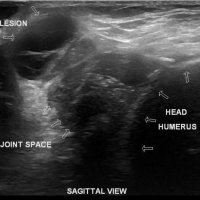

On physical examination, an AC joint cyst is a palpable fluid-filled mass. MRI scanning or a shoulder arthrogram should be obtained to evaluate the shoulder. Unenhanced MRI scans showing a large rotator cuff tear, a degenerated AC joint, and a large subcutaneous cyst adjacent to the AC joint is virtually patognomonic for the disease. Contrast administration on MR arthrogram will show the synovial fluid or intra-articular contrast extravasates from the glenohumeral joint into the subacromial bursa, into the AC joint, and then into an overlying cystic mass when a full-thickness rotator cuff tear is present, resembling a geyser spouting upwards.